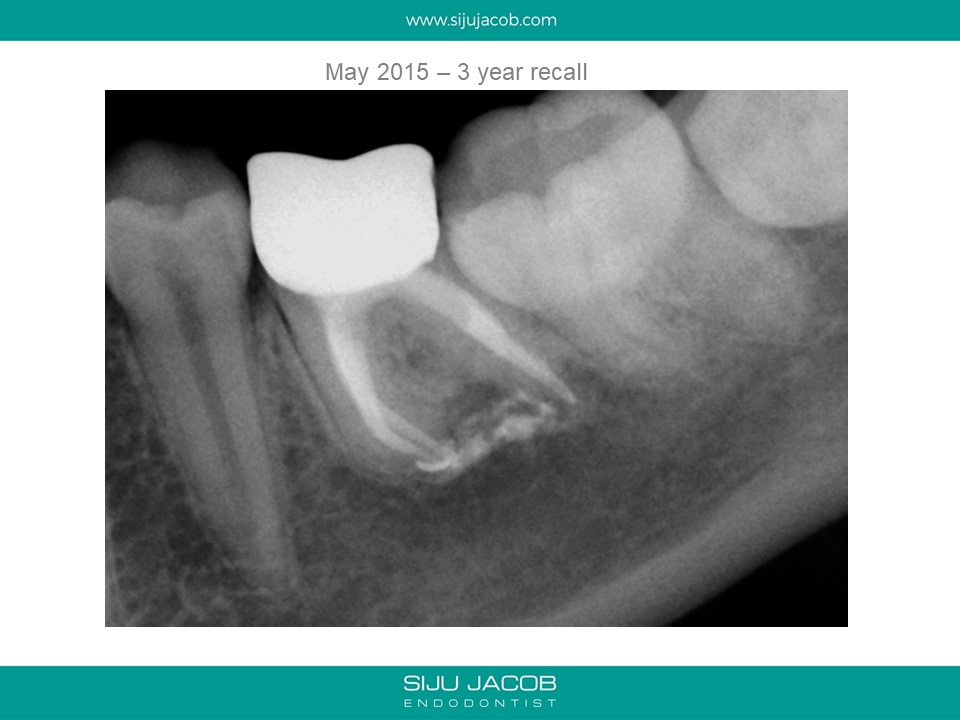

This was a 15 year old girl with a large peri-apical lesion in relation to the the left mandibular first molar. The tooth had a guarded restorative prognosis. The goal of endo in this case was to hold the tooth for a longer period before placing implants and also get some bone to fill in which would make implant placement more viable. I held the tooth with calcium hydroxide dressing for 5 months, saw some bone-fill and obturated the tooth. A crown was also placed. 3-year recall shows the tooth still going strong.